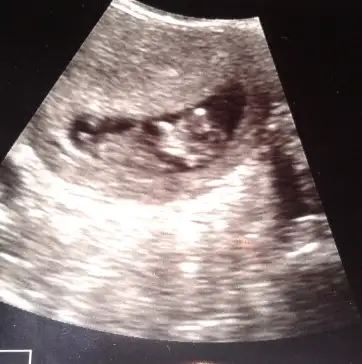

Kizlar yorum yapar kemik yapisina keseye gore..ama nub gormedim sanki ya da tecrubesizligimdennnnbenim bebeğimede bir bakarmısınız? fotografta 12+3 günlük

ya benim bebeğim cinsiyeti tahmin eden var mi? erkeğe benziyor dedi ama kesin degil dedi bi doktor da kız gibi kafam karisti

Senin bebikte kiza benziyobenim bebeğimede bir bakarmısınız? fotografta 12+3 günlük

Kesine yakin kiz diyorum